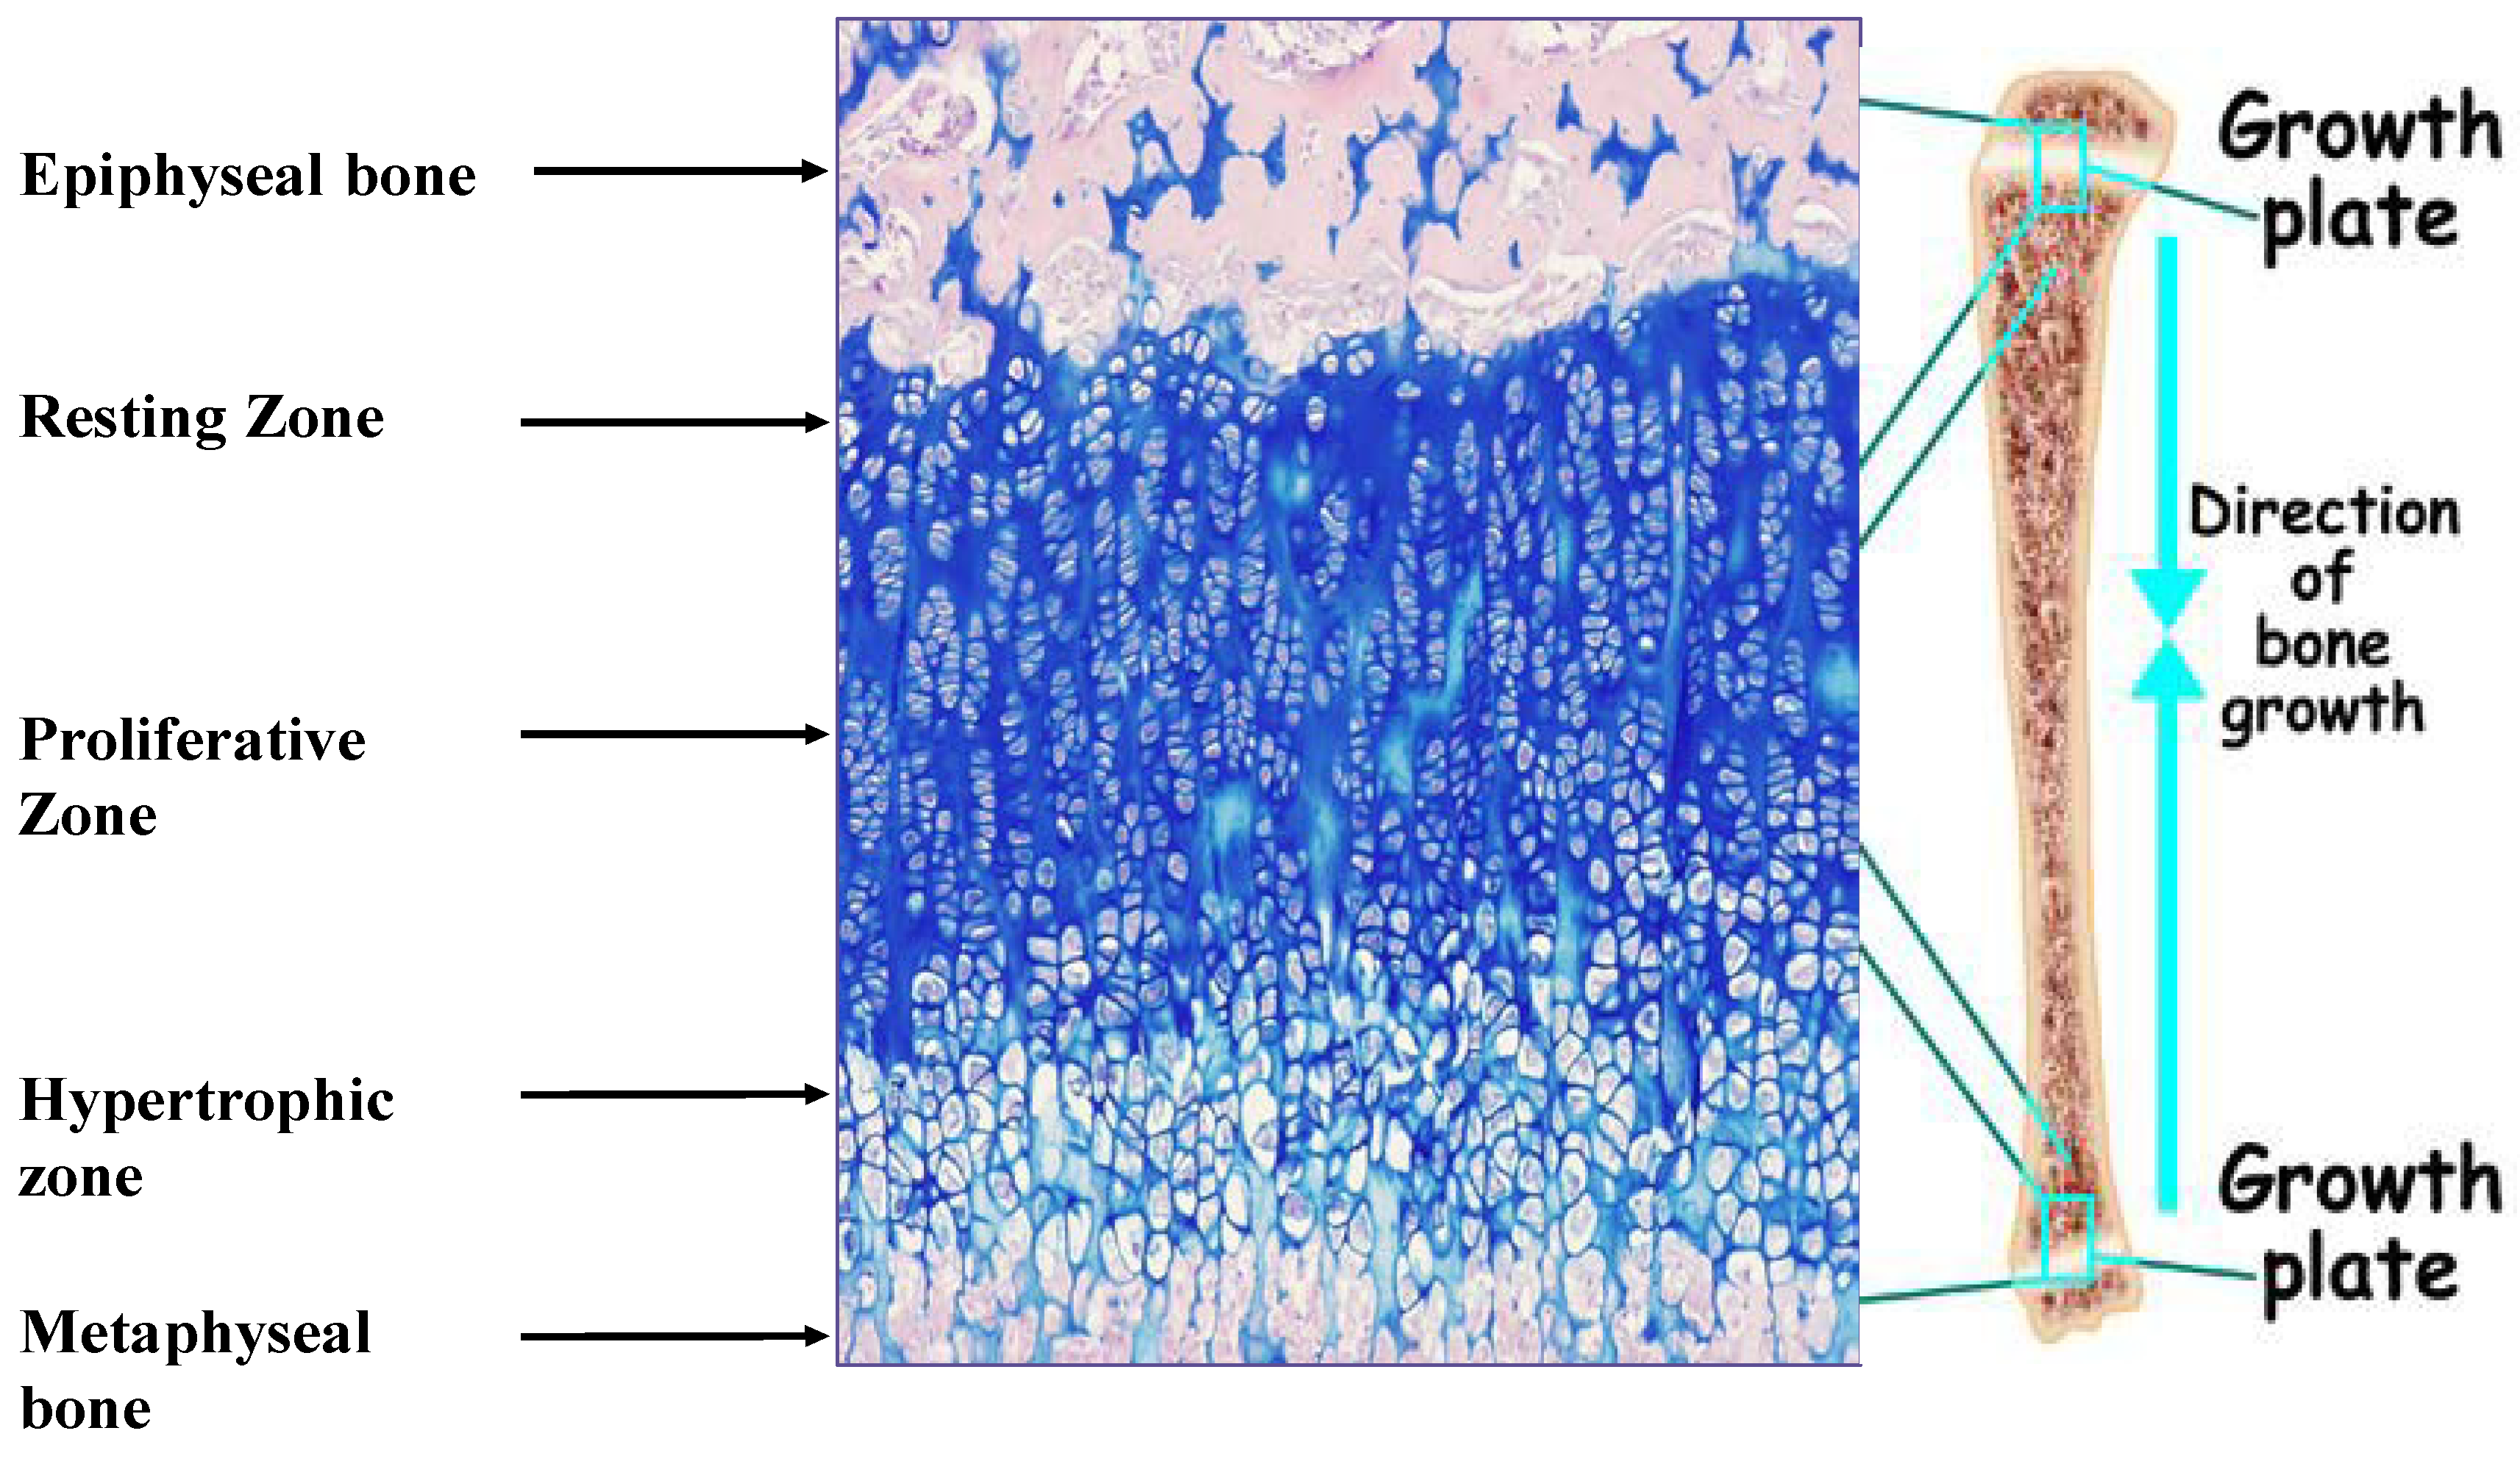

Linear growth of the appendicular skeleton is the product of a cascade of events that take place in the cartilaginous growth center of the long bones, termed the epiphyseal growth plate (EGP) (Figure 1). It is controlled by complex interactions among hormones, local growth factors and components of the extracellular matrix (ECM). The process is driven by the chondrocytes. It begins with the proliferation of resting early chondrocytes located at the most epiphyseal end of the EGP, followed by their alignment in columns parallel to the long axis of the bone. The cells then undergo a period of high secretory activity, depositing the cartilage ECM components, including collagens, proteoglycans and other materials, until their maturation into hypertrophic chondrocytes. The transition from cell proliferation to hypertrophy takes place in the pre-hypertrophic zone located in the middle of the EGP. Several important regulatory molecules, such as Indian hedgehog (Ihh) and the parathyroid hormone-related protein (PTHrP) receptor, are expressed specifically in this region [2]. Once the hypertrophic cells cease dividing, they increase in volume by 5–10-fold owing to the ingress of water and begin to secrete ECM, consisting of collagen type X, as well as small matrix vesicles that serve as centers of mineralization. Thereafter, the chondrocytes undergo programmed physiological cell death [3], with calcification of the ECM. Blood vessels, osteoclasts and osteoblasts are now able to enter the ECM, and the cartilage scaffold is replaced with bone tissue. The reorganization of the ECM is crucial to the proper development of the EGP [4].

Figure 1.

Epiphyseal growth plate of male Sprague Dawley rat (34 days old) stained with hematoxylin/eosine/Alcian Blue. Magnification, 100×. The different zones of the growth plate are marked.